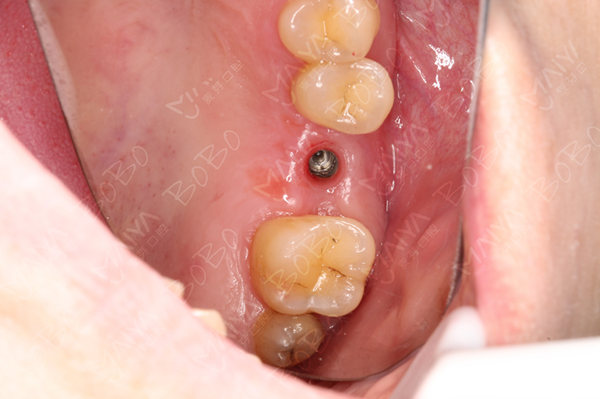

种植体的植入